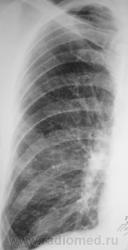

Следующее плановое исследование.

После проведения данного исследования возникло подозрение, что "это" не туберкулёз, или имеет место сочетанная патология.

После первой госпитализации в областном спец. ЛПУ, при выписке, в виде контроля динамики, была сделана рентгенограмма в прямой проекции, которая, на мой взгляд, имеет определенный интерес.